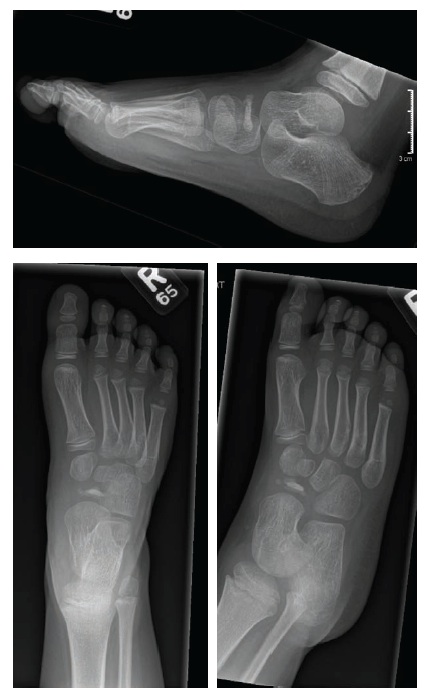

Radiography was performed, the results of which are shown here.

Posteroanterior, lateral, and medial oblique radiographs of the foot showed flattening, sclerosis, and some fragmentation of the tarsal navicular bone, which correlated with the location of tenderness. It appeared as if the bone had collapsed, reminiscent of the appearance of the capital femoral epiphysis in Legg-Calvé-Perthes disease.

The boy’s history, physical examination findings, and radiography results were diagnostic for Köhler disease, or avascular necrosis of the tarsal navicular. No further tests were indicated.1

Seemingly miraculously, this necrotic bone recovers completely,2-4 perhaps because, as can be seen in this patient’s radiographs, the thick circumferential cartilage preserves and protects the space needed for the navicular bone. Within that cartilage lies a rich arterial anastomosis.